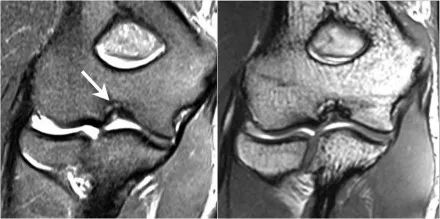

下面的图我们看到UCL的两个连续冠状图像。在近端部分(箭头)看到一些高信号是正常的。注意它是如何牢固地附着在崇高的结节上并将其与下一个图像进行比较。

请记住,UCL应该非常紧密地附着在崇高的结节上。在下面这种情况下它没有,所以即使在这两个图像上你也可以看出它有完全的撕裂。请注意,崇高结节中存在一些骨髓水肿。